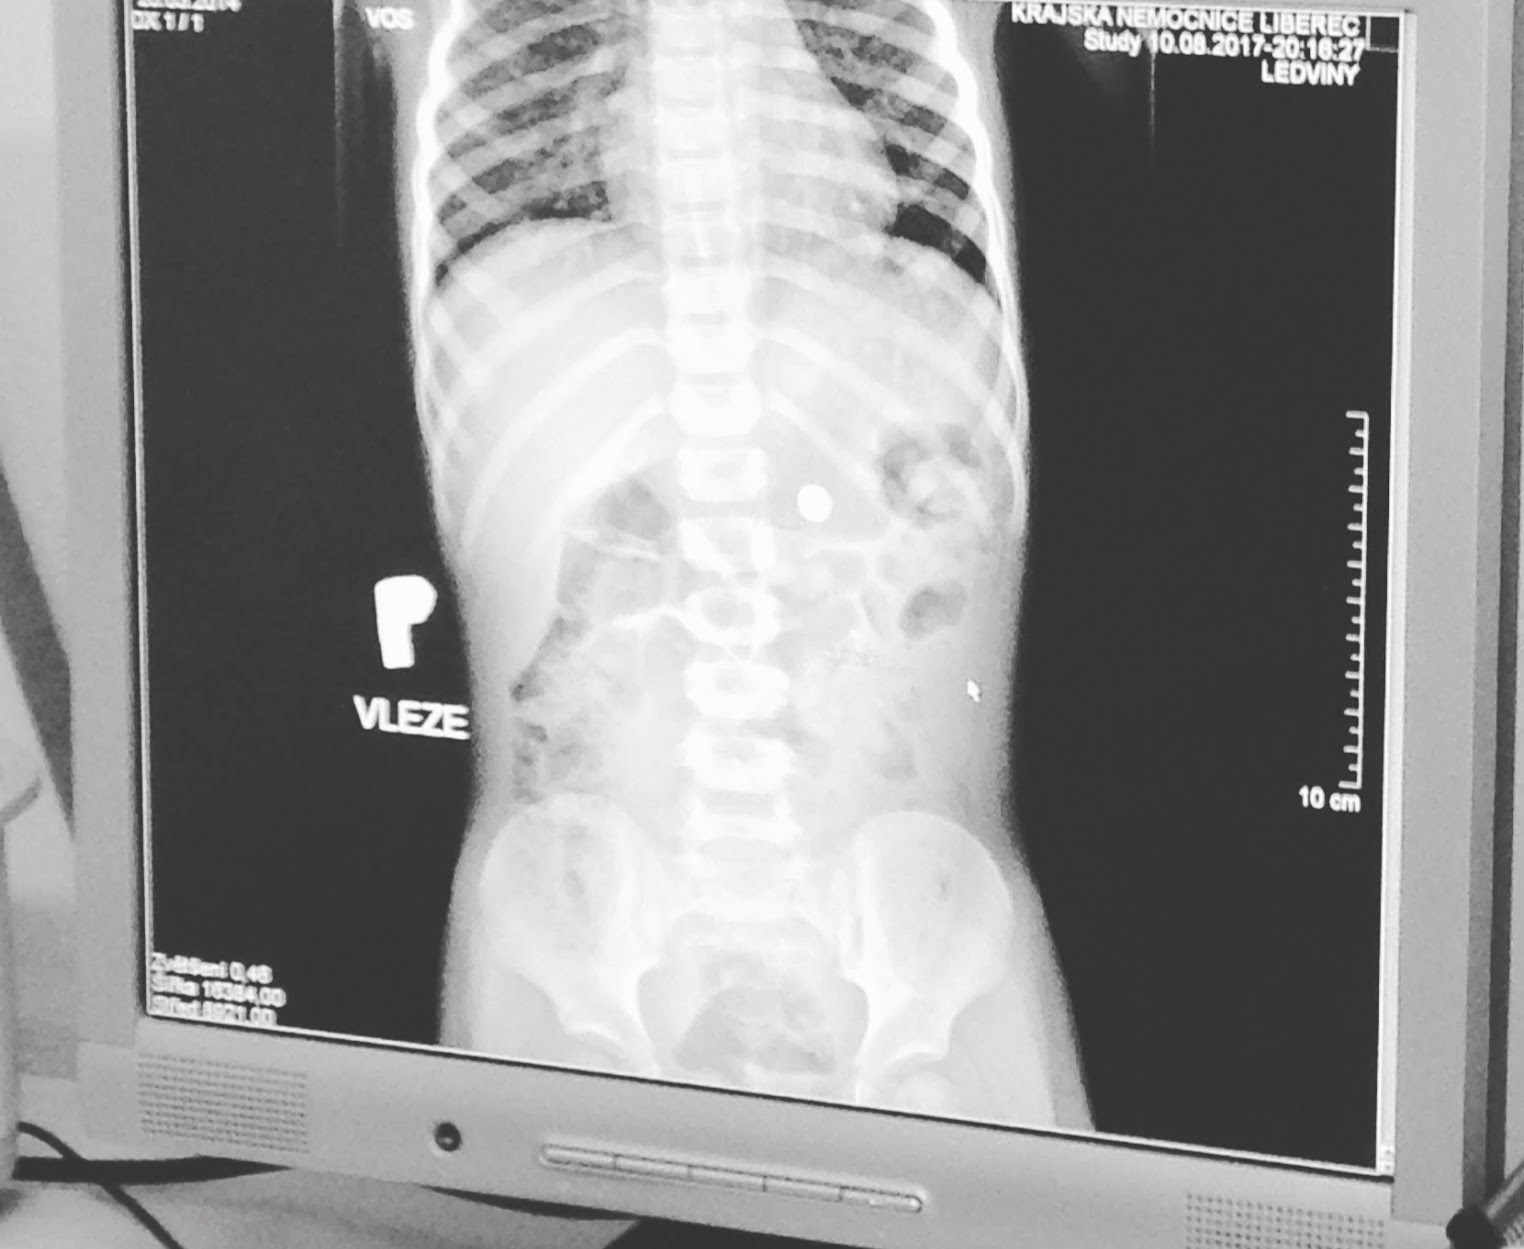

Pod přistávací plochou pro vrtulníky přecházíme na radiologii. Taky nás hned berou, Sárka si nechá udělat cvak, a hned jak dorazíme zpátky, už mají snímek v počítači. Baterie je v žaludku.